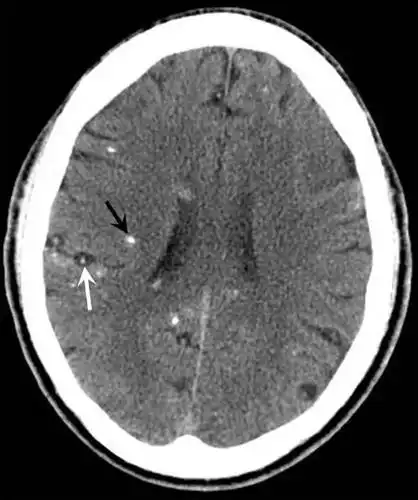

一文读懂:脑囊虫病的影像学表现